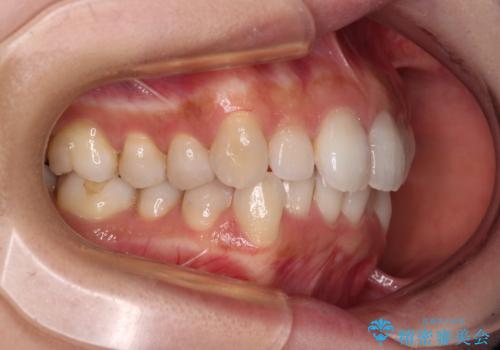

- デコボコと飛び出している前歯を気にして来院された患者様です。

歯列としてはインビザラインでもワイヤー矯正でも対応できるものでしたが、奥歯の咬み合わせを見た時に上顎がやや前方にあり、インビザライン単独では時間のかかってしまう可能性があるため、補助装置を治療当初に使用することで、インビザラインによる治療をスムーズに行えるように計画しました。